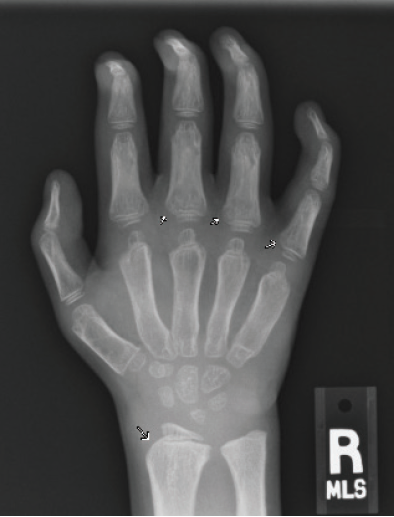

Figure 3A. Posteroanterior radiograph of the left hand.

Figure 3B. Posteroanterior radiograph of the right hand. Posteroanterior radiographs of both hands demonstrate fixed contractures of the distal interphalangeal joints, slightly “bullet-shaped” phalanges with osteopenia, broadening of the metacarpals, and dysplastic appearance of the distal radii.

There were multiple abnormalities noted in several of these images. The hips and pelvis were noted to have bilateral coxa valga, and the lateral aspects of both femoral heads were incompletely covered by the acetabulae. His sacroiliac joints were noted to be widened, and the lumbar spine demonstrated shortened height of the vertebral bodies. There was soft tissue swelling or redundancy at the bilateral wrists and decreased bone mineralization. Images of his elbows showed loss of skin folds at the bilateral anterior elbows consistent with soft tissue swelling, possibly related to chronic contractures. Views of his hand showed moderate fixed flexion of the bilateral DIP joints along with bilateral soft tissue swelling, enlargement, osteopenia and gross abnormalities (Figures 3A and 3B). The lumbar spine images showed vertebral body height loss as well as posterior vertebral body scalloping most pronounced at the lower lumbar spine. It was also noted that on the anteroposterior view there was demonstration of possible hepatomegaly. Overall, interpretation by pediatric radiology noted that the findings raised concern for a possible underlying genetic disorder.